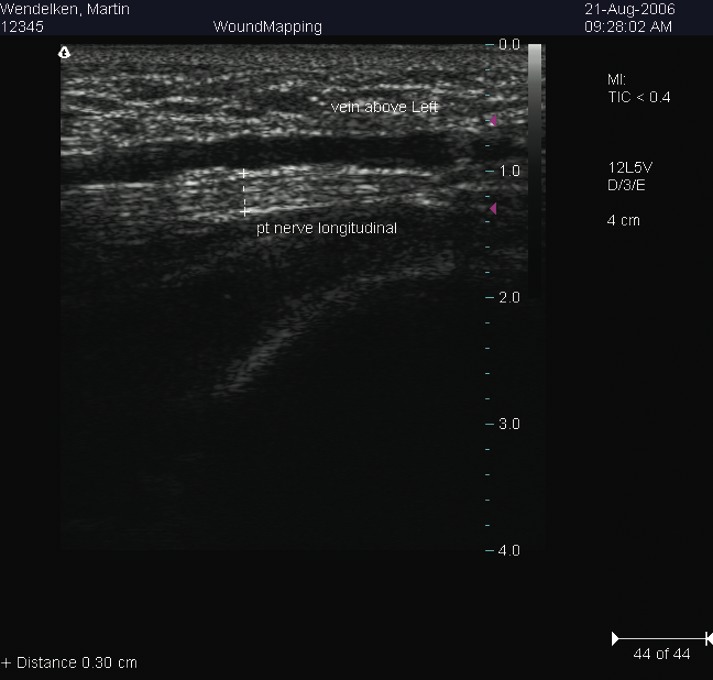

Combining Cryosurgery With Ultrasound: A Guide To Surgical Technique

The procedure involves palpating the posterior tibial artery just proximal to the level of the medial malleolus. We begin by providing anesthesia using a 1 cc syringe of 1% lidocaine with 100,000 dilution of epinephrine. One would inject this solution subcutaneously with a tuberculin syringe 2.5 cm superior to the medial malleolus directly over the posterior tibial artery. We proceed to prep the area in the usual sterile manner with Betadine® and protect the area with a Sound-Seal® thin film dressing (BioVisual Technologies), an FDA-approved protective film dressing for diagnostic ultrasound exams. Cover the area with the sterile dressing and mark the incision site using a sterile pen. A #11 sterile blade provides for a transverse 3 mm full-thickness skin incision. Take care not to violate any deeper structures. (In the aforementioned case study, we performed the procedure in the office under local anesthesia and without tourniquet assistance.) Using a blunt probe, gently penetrate the fascial tissue in the direction of the neurovascular bundle. Use the diagnostic ultrasound machine carefully to help create a tunnel for the cryosurgery probe. Insert the probe into the incision site while under the guidance of the diagnostic ultrasound scanner. We use the HydroStep® Standoff pad to help facilitate compliance over bony prominences such as the medial malleolus. The standoff pad also moves vital structures into specific ultrasound focus zones. The combination of compliance and the shifting of structures deeper into focus zones provides better image quality and resolution. Proceed to introduce the probe into the target area, namely the posterior tibial neurovascular bundle. Since the cryosurgery ice ball ranges in size of 3.5 to 10 mm, depending on environmental conditions, there is no need to dissect the nerve from its adjacent vein and artery. After inserting the probe with pressure directly on the neurovascular bundle, the freezing technique begins. This involves a three-minute freeze cycle, which causes an ice ball formation around the neurovascular bundle. One can directly visualize this process in real time using diagnostic ultrasound imaging. After the initial three-minute freeze, perform a 30-second thaw cycle followed by a second three-minute freeze cycle and 30-second thaw cycle. Generally, the ice ball will surround most of the neurovascular bundle as one can see on the diagnostic ultrasound screen. Once this cycle is completed, withdraw the probe. Dress the incision site with a sterile antibiotic ointment and a gauze compression dressing. No sutures are needed. Our general postoperative course involves no medications and no limitation of activity. The patient is able to shower the following day.